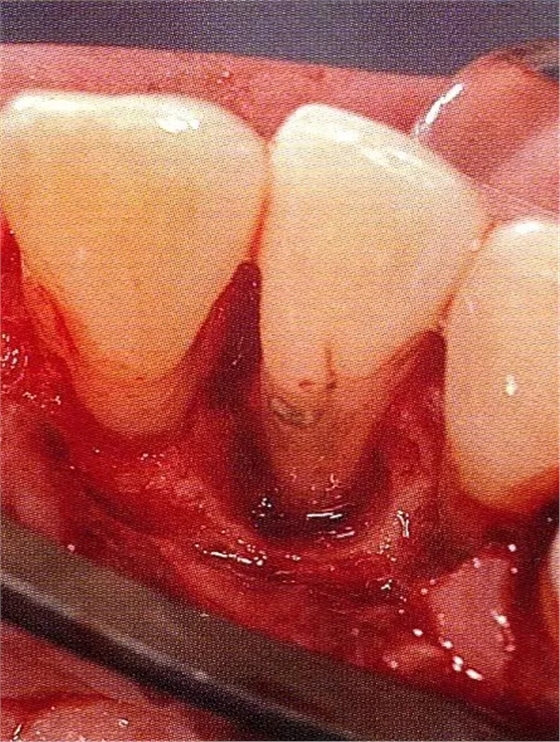

▲圖7-3將posterior interproximal類型的非吸收性覆膜修整后進(jìn)行垂直懸吊縫合做固定。垂直懸吊縫合后,確定覆膜是否會(huì)動(dòng)搖,再將齦瓣與之緊密縫合。

▲圖7-4術(shù)后1年2個(gè)月再翻開看的情況。與圖7-1的骨缺損狀態(tài)相比可知形成了臨床性骨再生。